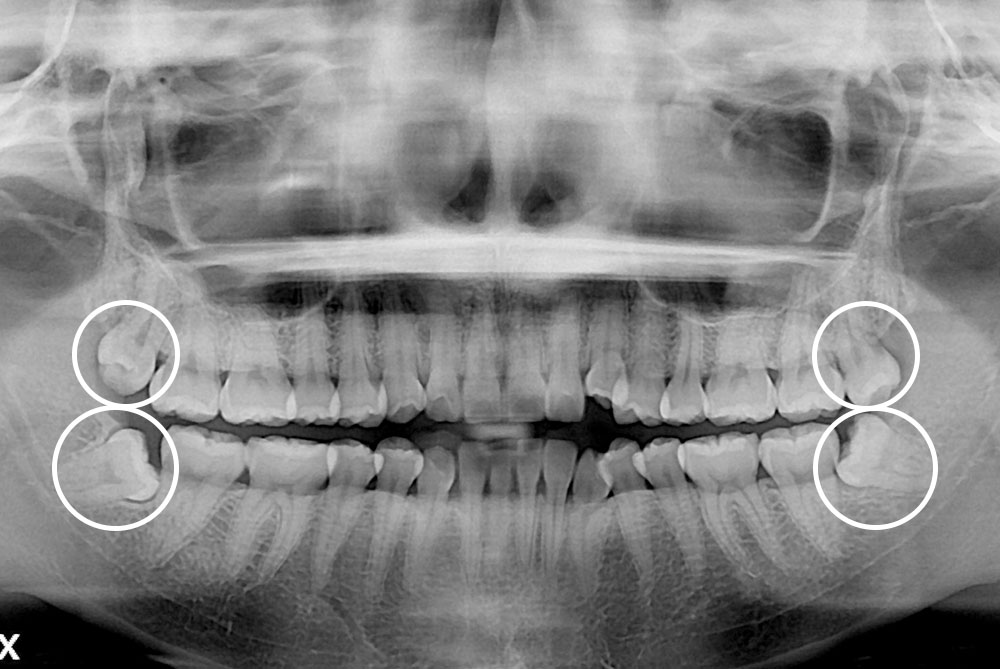

세종치과의 진심 어린 치료는 결과로 말합니다.

실제 내원하신 환자분들의 치료 전·후 사례를 확인해보세요.

모든 치료사례 전후사진은 환자분의 동의하에 촬영되었습니다.

모든사진은 동일 환자분의 전후모습을 촬영하였으며, 사진의 밝기조절 외에 임의 수정이 없음을 알려드립니다.

*수 / 시술 후 개인에 따라 결과의 차이 및 감염 등 부작용이 발생할 수 있으므로 의료진과 충분한 상담 후 결정하시길 바랍니다.